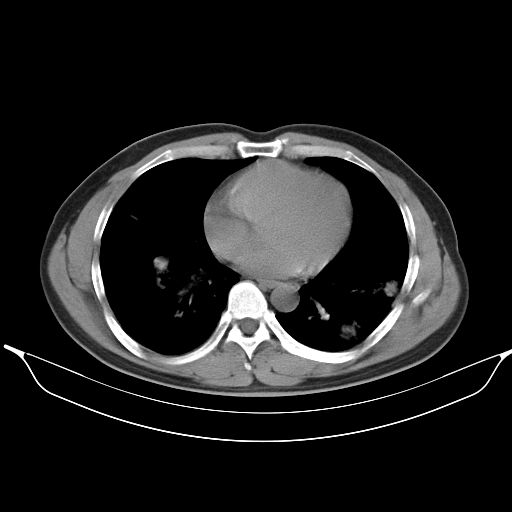

标题: CT25490:男,40岁,体检发现;无其它不适。 [打印本页]

标题: CT25490:男,40岁,体检发现;无其它不适。

考虑右下肺周围性肺癌并肺内多发转移,纵隔淋巴结转移!

支持 !考虑右下肺周围性肺癌并肺内多发转移,纵隔淋巴结转移,(气管前腔静脉后,隆突下,主动脉弓下都有了)